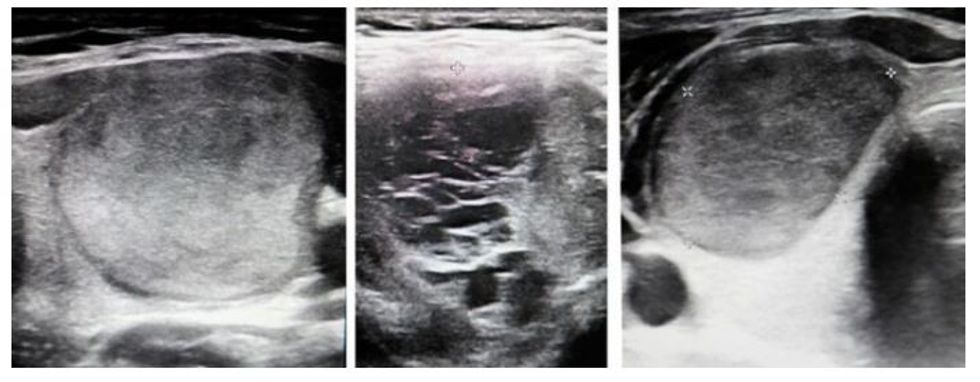

Gjëndra tiroide është një gjëndër endokrine e vogël por jashtëzakonisht e rëndësishme, gjendet në pjesën e përparme të qafës dhe luan një rol kyç në ruajtjen e ekuilibrit të përgjithshëm në trup. Nyjet, të njohura edhe si nyjet e gjëndrës tiroide, paraqesin ndryshime fokale, të kufizuara, ndryshime fizike në indin e tiroides, me dimensione të ndryshme që mund të diagnostikohen me ekzaminim ultrasonografik të gjëndrës dhe përshkruhen karakteristikat e tyre ekografike. Ekzistojnë ndarje të shumta të nyjeve. Sipas numrit të tyre, ato mund të jenë të vetme ose të shumëfishta, ndërsa sipas funksionit – funksionale ose jofunksionale, sipas strukturës së nyjës dhe se cili komponent dominon, ato ndahen në nyje solide dhe cistike. Sipas natyrës së tyre, ato ndahen në beninje dhe malinje. Arsyeja e shfaqjes së nyjeve nuk është konkrete dhe e qartë, por besohet se gjenetika, autoimuniteti dhe ndikimet e jashtme luajnë një rol në patogjenezën e tyre.

Nyjet rriten ngadalë – sa gjatë monitorohen, në çfarë intervalesh duhet të kontrollohen dhe kur merren masa konkrete për trajtimin e tyre? Dr. Mihajlovska: Ndryshimet nodulare të gjëndrës tiroide zakonisht janë me rritje të ngadaltë dhe kërkojnë monitorim të rregullt dhe afatgjatë të ndryshimeve, përkatësisht dimensionit të tyre, pamjes, karakteristikave ekografike, si dhe faktorëve indirekt që ndikojnë në planin e trajtimit të këtyre ndryshimeve. Këtu nuk përfshihen ndryshimet me rritje të shpejtë, të cilat janë kryesisht të natyrës së keqe. Kjo do të thotë se kanë nevojë për diagnozë dhe trajtim të shpejtë dhe në kohë.

Kryesisht, çdo ndryshim i shpejt i dimensioneve ose karakteristikave kerkon diagnostikim shtesë, më të thellë. Kjo nënkupton kryerjen e punktimit (shpimit) me gjilpërë të imët, që do të na japë një pamje të përgjithshme qelizore të natyrës së nyjës. Dimensioni në të cilin të gjitha nyjet në parim duhet t’i nënshtrohen punktimit është 10 mm. Por ndonjëherë mbetet e drejta ekskluzive e mjekut, në varësi të karakteristikave të nyjës, të vendosë nëse do të rekomandojë punktim të nyjes me dimension 5 mm apo të presë një rritje të tyre deri në 10-15 mm.